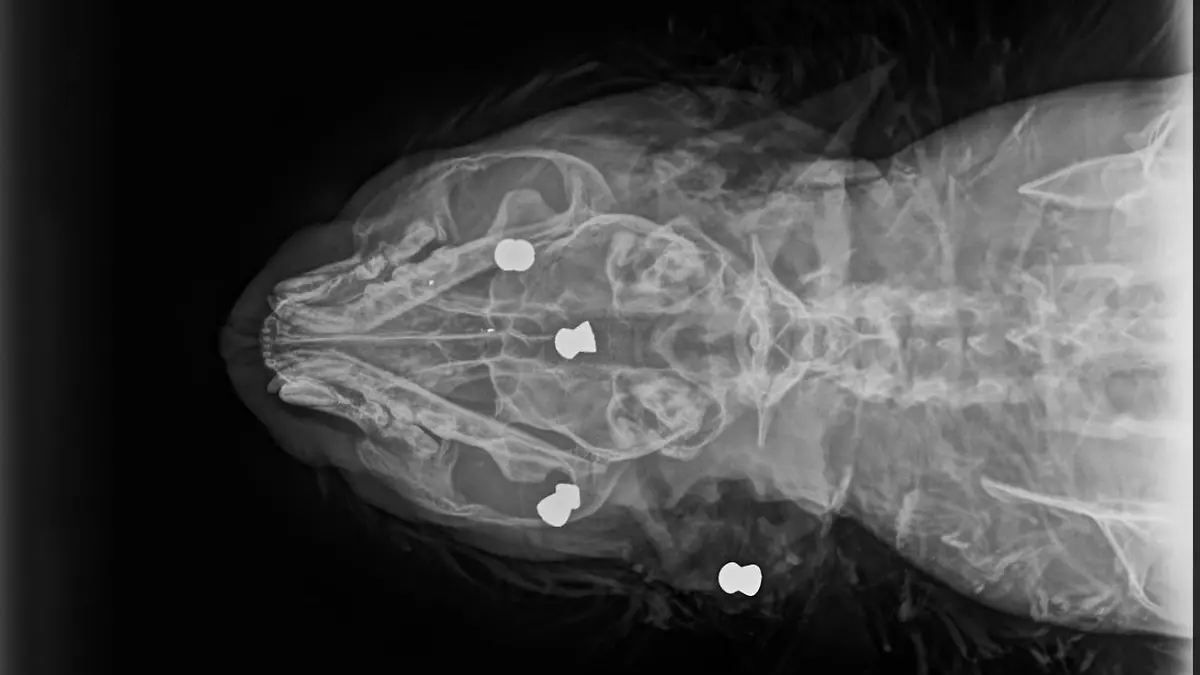

Der Grund: Das Tier hat fünf Kugeln in seinem Körper stecken – eine im Rücken, vier im Kopf. „Die Herzfrequenz war schon sehr, sehr verlangsamt. Dann habe ich gesehen, dass er die Geschosse in sich trägt, vor allem halt im Kopf. Das ist mit dem Leben so nicht mehr vereinbar gewesen. Der Kater war schon im Sterbeprozess.“ Um das Leid des Tieres nicht unnötig zu verlängern, haben sich Choucair und sein Team dazu entschieden, ihn einzuschläfern.

Der unkastrierte Kater war gerade einmal anderthalb Jahre alt und in einem guten Pflegezustand. Auch deshalb dachte Choucair zuerst, dass es sich um einen Autounfall handeln könnte. „Erst nach den Röntgenbildern habe ich das Ausmaß der Verletzungen abschätzen können. Also unseres Erachtens nach ist der Kater schlussendlich durch Menschenhand brutal hingerichtet worden. Anders kann man das nicht bezeichnen“, so der Tierarzt.

Zwar habe er schon häufiger gesehen, dass Diabolo-Geschosse - die Patronen aus einem Luftgewehr – Tiere verletzt hätten. Doch bei einem solchen Bild müsse man von einer furchtbaren Misshandlung sprechen. „Hier sind auch Tränen seitens der Mitarbeiter geflossen, weil das absolut nicht alltäglich ist. Das stimmt schon nachdenklich, dass es Mitmenschen auf dieser Welt gibt, die so etwas machen.“